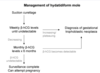

How do you manage PPROM when it occurs ≥ 34WG?

How do you manage [PPROM < 34 WG] when it occurs

How do you manage Preterm Labor 34 to 36+6 WG - 2